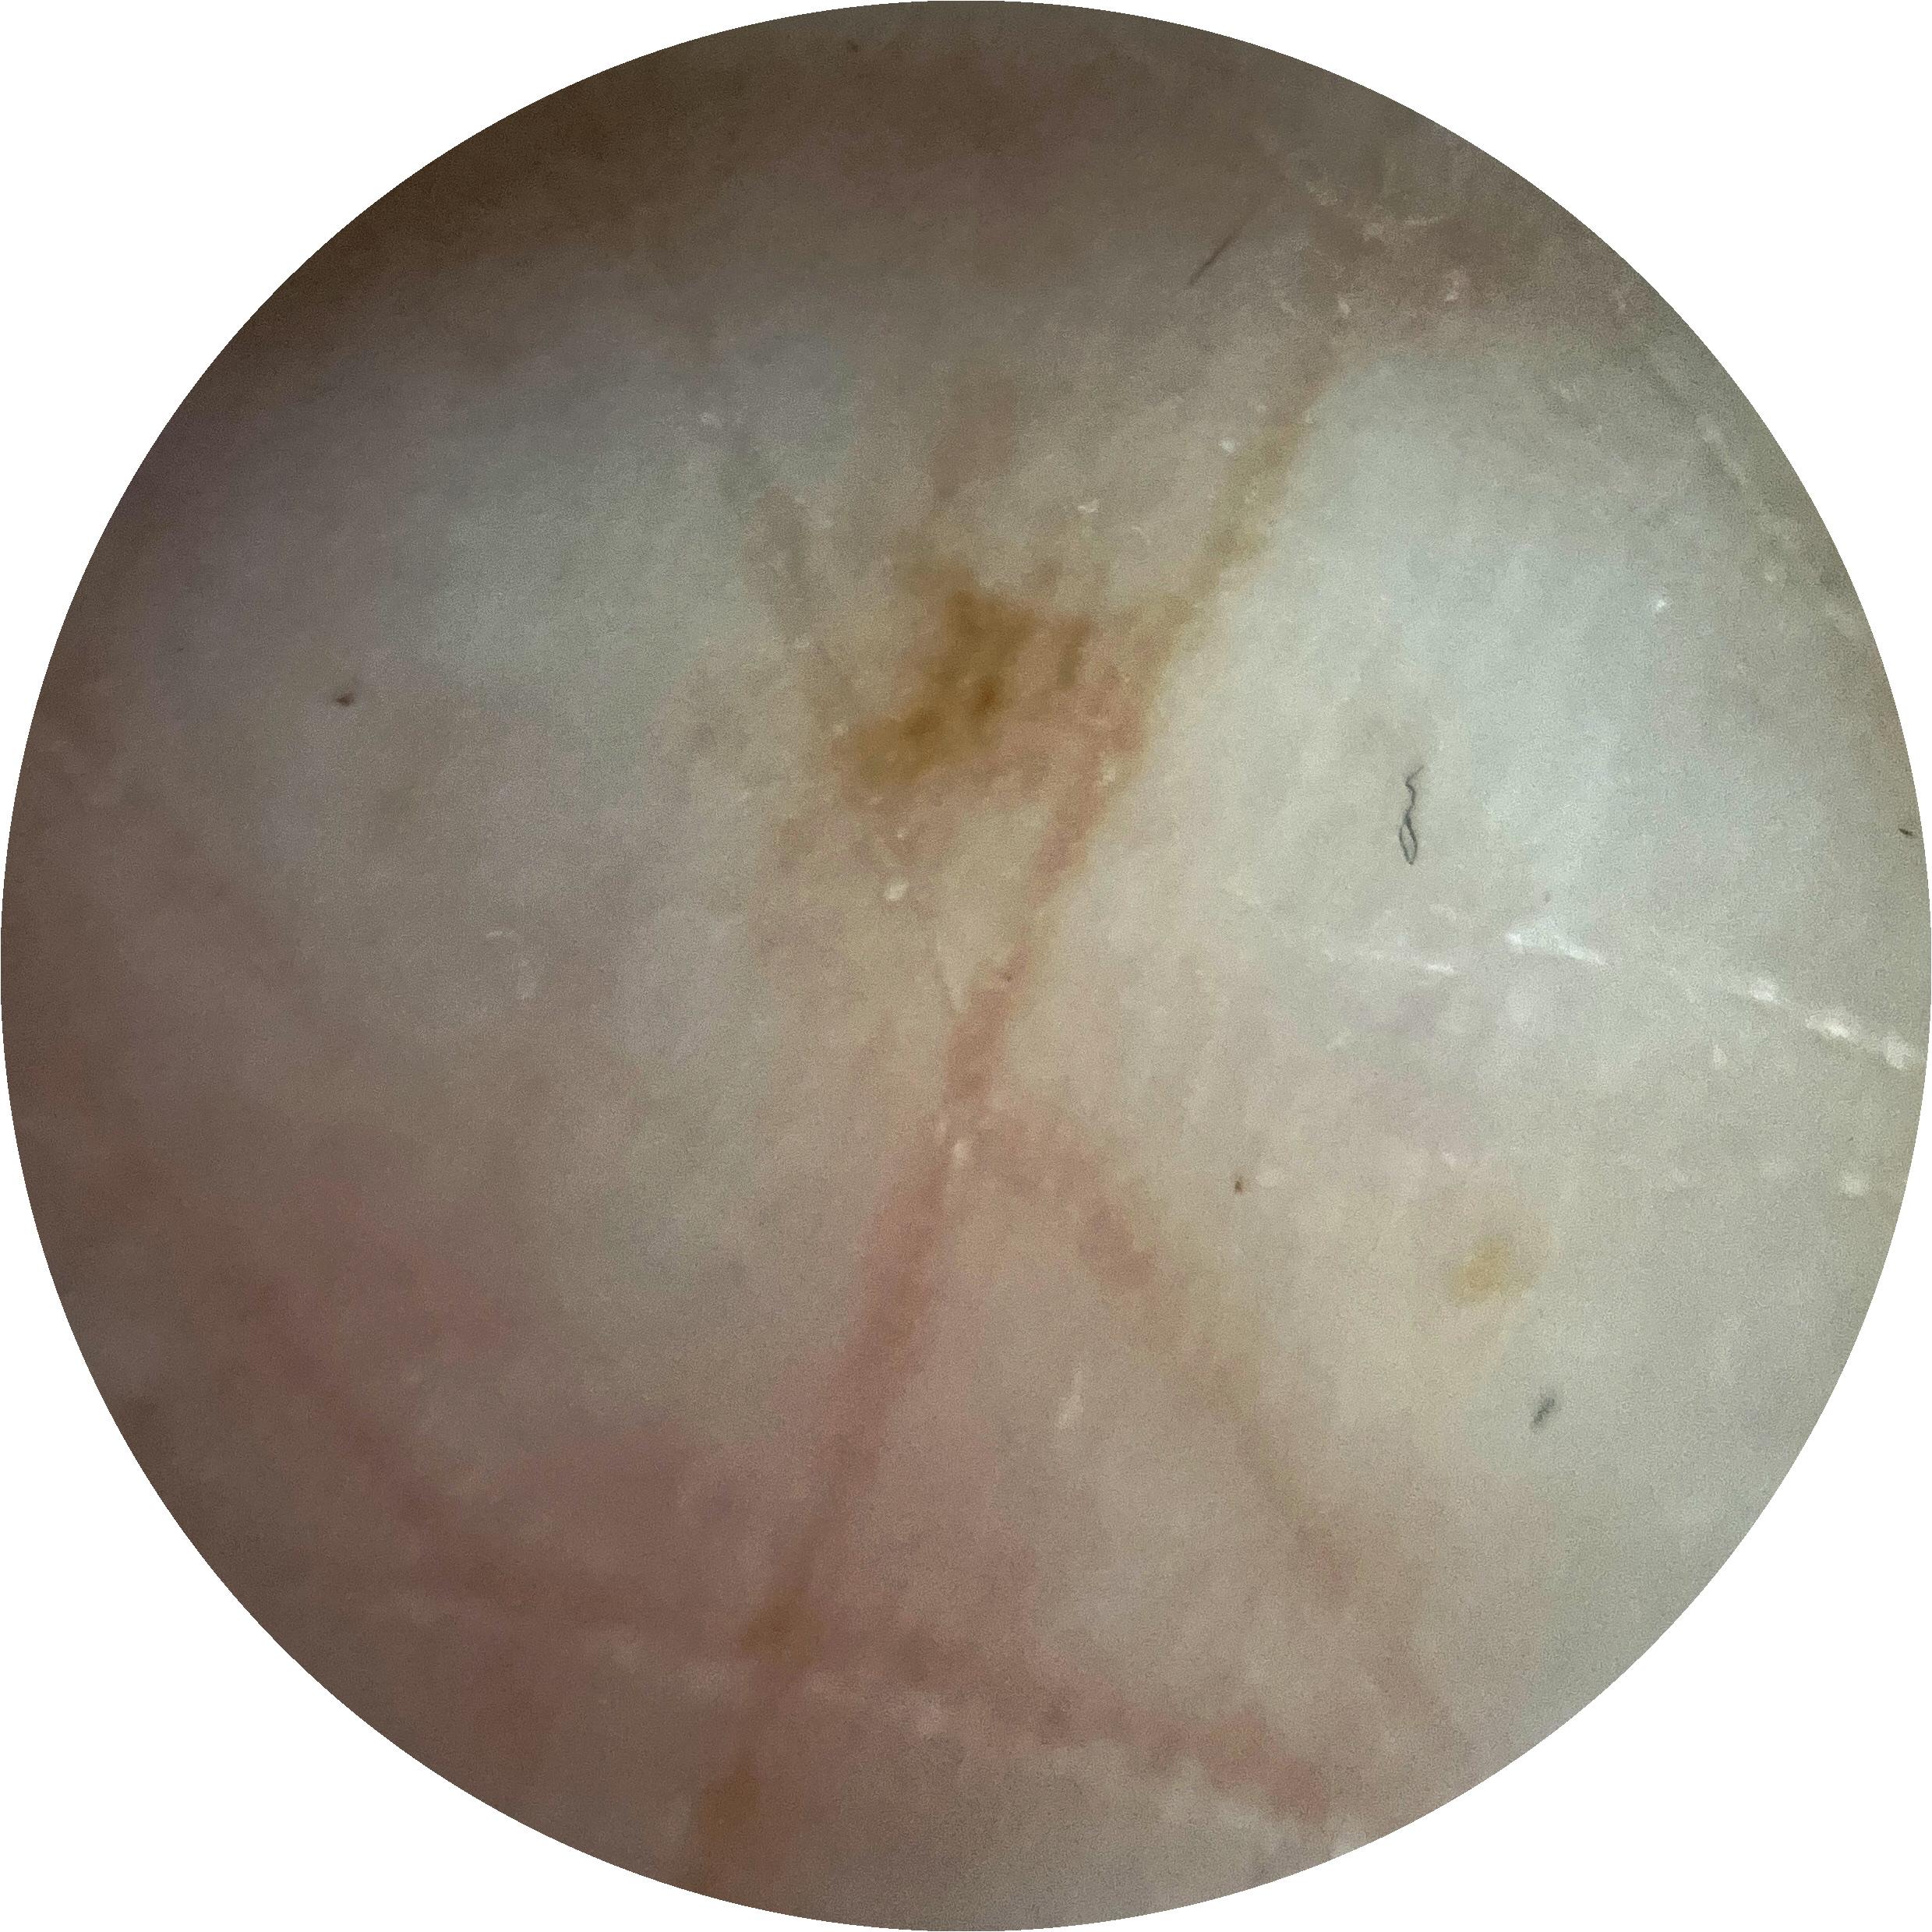

ISIC_7213120

Clinical

Field Value

acquisition_day 277

age_approx 70

anatom_site_1 Lower extremity

anatom_site_general lower extremity

diagnosis_1 Benign

family_hx_mm True

fitzpatrick_skin_type I

image_manipulation instrument only

image_type dermoscopic

lesion_id IL_3605610

patient_id IP_0257923

personal_hx_mm True

sex female